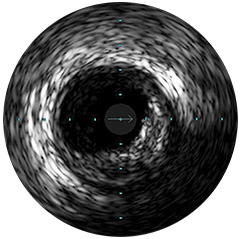

Digital IVUS imaging

imaging

imaging

imaging

Orientación IVUS

es "definitivamente beneficiosa" para los pacientes, y dio lugar a un cambio de los planes de tratamiento el 74% de las veces 1,6,7